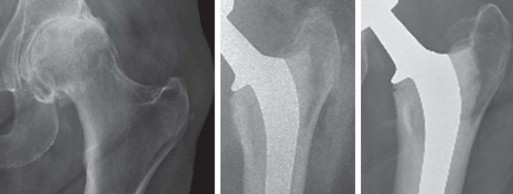

ألم الورك المزمن، الذي يقيد حركتك ويُسرق منك متعة الحياة اليومية، ليس قدرًا لا مفر منه. في عالم اليوم، ومع التقدم الهائل في الجراحة العظمية، أصبح استبدال مفصل الورك الكلي (Total Hip Replacement - THR) حلًا جذريًا يعيد إليك حريتك في الحركة ويُنهي معاناتك مع الألم. تُعد تقنية الإسمنت للفخذ في جراحة استبدال مفصل الورك من الإجراءات الرائدة التي أثبتت فعاليتها على مدى عقود، خاصة للمرضى الذين تتطلب حالتهم استقرارًا فوريًا وثباتًا طويل الأمد.

تقنية الإسمنت للفخذ، التي تُعد محور حديثنا، هي طريقة راسخة لتثبيت المكون الفخذي (الجزء الذي يتم إدخاله في عظم الفخذ) من المفصل الصناعي باستخدام إسمنت عظمي خاص. يضمن هذا الإسمنت استقرارًا فوريًا وقوة تحمل عالية، مما يجعله خيارًا ممتازًا للعديد من المرضى، وخاصة كبار السن وذوي العظام الضعيفة. ستكتشف في هذا الدليل لماذا تُعد هذه التقنية خيارًا موثوقًا به، وكيف يمكن أن تُحدث فرقًا حقيقيًا في حياتك.